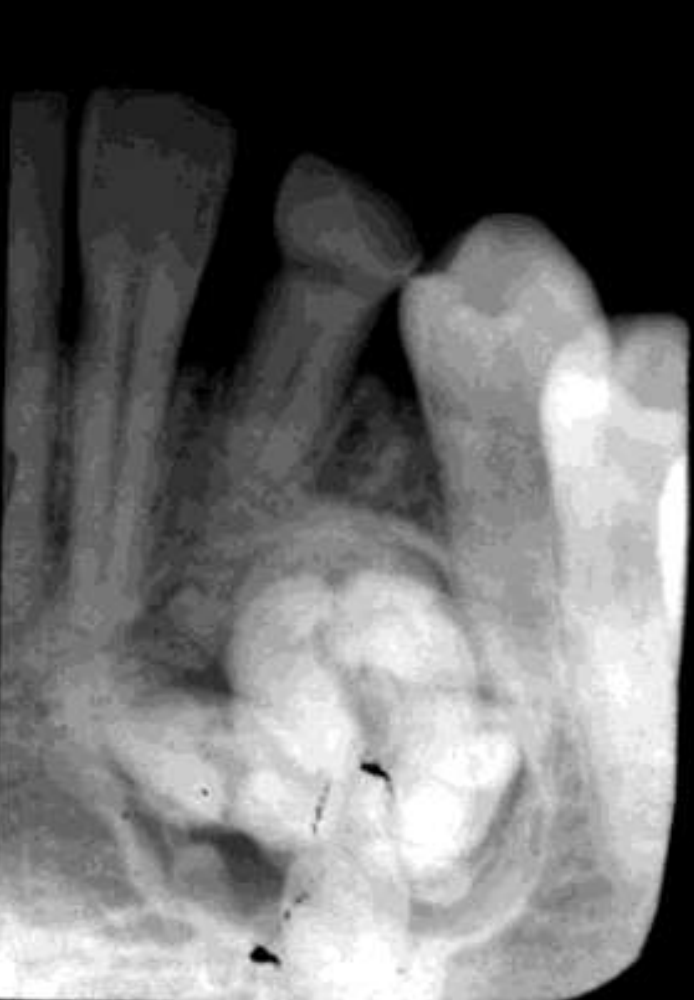

cementoblastoma

how do cementoblastomas present radiographically?

Multiple punctate radiopacities within a welldefined radiolucency

Homogeneous radiopaque mass

Mass attached to 1st mandibular molar roots

Obscured root outline, resorption

Radiolucent halo - continuity with PDL

Sclerotic border

cementoblastomas

external root resorption 30

displacement of IAN canal inferiorly

thinning/expansion of inferior border of mandible